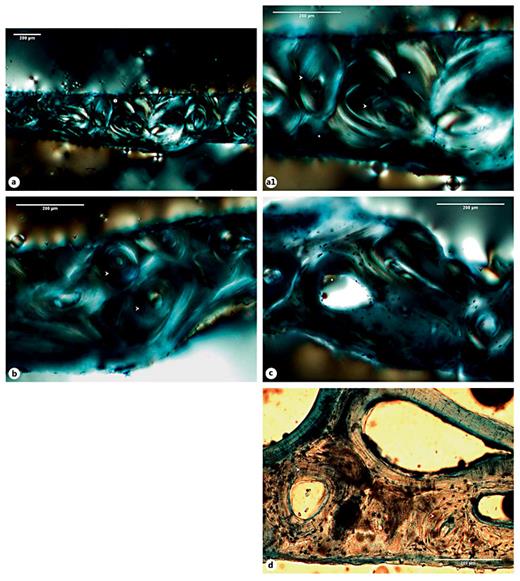

A remodeled callus microstructure characterized by well-defined osteons and interstitial lamellae was also identified in the right rib sample retrieved from Sk. 1,196. In this sample, multiple bays of bone resorption were observed in the endosteal and periosteal surfaces. At some points, larger areas of bone resorption enclosed by thin layers of bone lamellae were seen, in addition to enlarged Haversian canals and numerous osteocyte lacunae (fig. 7a-d). In contrast with the above-mentioned case, the sample retrieved from the right radius of the same Sk. 1,196 individual showed a more immature microstructure. For example, an intricate network of trabeculae, some of them with signs of bone resorption, was observed in the posterior side of the bone callus. The typical structure of a mature cortical tissue was recorded as absent from the core of the bone callus, as well as from the opposite anterior surface. That is, no clearly defined osteons, interstitial lamellae, and Haversian canals were observed. Instead, the anterior portion appeared to be formed by horizons of lamellar bone pinpointed by a high density of osteocyte lacunae, which suggests distinct levels of bone deposition. Irregular lines running alongside the bone lamellae were also seen. Finally, a pattern of disorganized lamellae and immature bone populated by osteocyte lacunae and separated by irregular areas of bone resorption and discrete Haversian canals was seen in the interface between the anterior and the posterior surfaces of the bone callus (fig. 8a-e1). The most striking example of an immature callus microstructure came from the Sk. 198 sample. In spite of the healed macroscopic appearance, the histological study revealed a cortical tissue formed by an intricate system of lamellae, comparable to trabeculae, in which multiple branches and islands of well-preserved lamellae connecting partially digested osteons were observed. A combination of mature lamellae with more immature bone populated by multiple osteocyte lacunae and large resorption spaces was also noticed. At the periosteal level, a rim of lamellae in distinct stages of maturation was seen bordering the outer surface of the bone (fig. 9a-d).

a Micrograph of the posterior portion of the SK. 1,196 right radius bone callus showing scattered trabeculae erased by foci of bone resorption (white arrowheads). b Illustration of the anterior portion of the callus revealing lamellar bone apposition with variable density and organization (white asterisks). c Another view revealing distinct layers of lamellae (white asterisks) separated by longitudinal lines (white arrowheads). d Area showing cortical lamellae mixed with more immature and disorganized forms of bone (white and black arrowheads), and spaces of bone resorption (white asterisks) and discrete vascular canals. e Segment exhibiting a haphazard arrangement of bone lamellae in distinct stages of maturation (white arrowheads), as well as enlarged resorption spaces (white asterisks). e1 Detail of the previous figure highlighting the orientation of the mineralized collagen fibers and the numerous osteocyte lacunae. Polarized light. Magnification ×40; ×100.

a Micrograph of the posterior portion of the SK. 1,196 right radius bone callus showing scattered trabeculae erased by foci of bone resorption (white arrowheads). b Illustration of the anterior portion of the callus revealing lamellar bone apposition with variable density and organization (white asterisks). c Another view revealing distinct layers of lamellae (white asterisks) separated by longitudinal lines (white arrowheads). d Area showing cortical lamellae mixed with more immature and disorganized forms of bone (white and black arrowheads), and spaces of bone resorption (white asterisks) and discrete vascular canals. e Segment exhibiting a haphazard arrangement of bone lamellae in distinct stages of maturation (white arrowheads), as well as enlarged resorption spaces (white asterisks). e1 Detail of the previous figure highlighting the orientation of the mineralized collagen fibers and the numerous osteocyte lacunae. Polarized light. Magnification ×40; ×100.